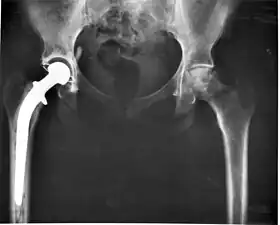

Some examples include pacemakers, infusion pumps, the heart-lung machine, dialysis machines, artificial organs, implants, artificial limbs, corrective lenses, cochlear implants, ocular prosthetics, facial prosthetics, somato prosthetics, and dental implants.

- Class III devices generally require premarket approval (PMA) or premarket notification (510k), a scientific review to ensure the device's safety and effectiveness, in addition to the general controls of Class I. Examples include replacement heart valves, hip and knee joint implants, silicone gel-filled breast implants, implanted cerebellar stimulators, implantable pacemaker pulse generators and endosseous (intra-bone) implants.

Medical implants

An implant is a kind of medical device made to replace and act as a missing biological structure (as compared with a transplant, which indicates transplanted biomedical tissue). The surface of implants that contact the body might be made of a biomedical material such as titanium, silicone or apatite depending on what is the most functional. In some cases, implants contain electronics, e.g. artificial pacemakers and cochlear implants. Some implants are bioactive, such as subcutaneous drug delivery devices in the form of implantable pills or drug-eluting stents.